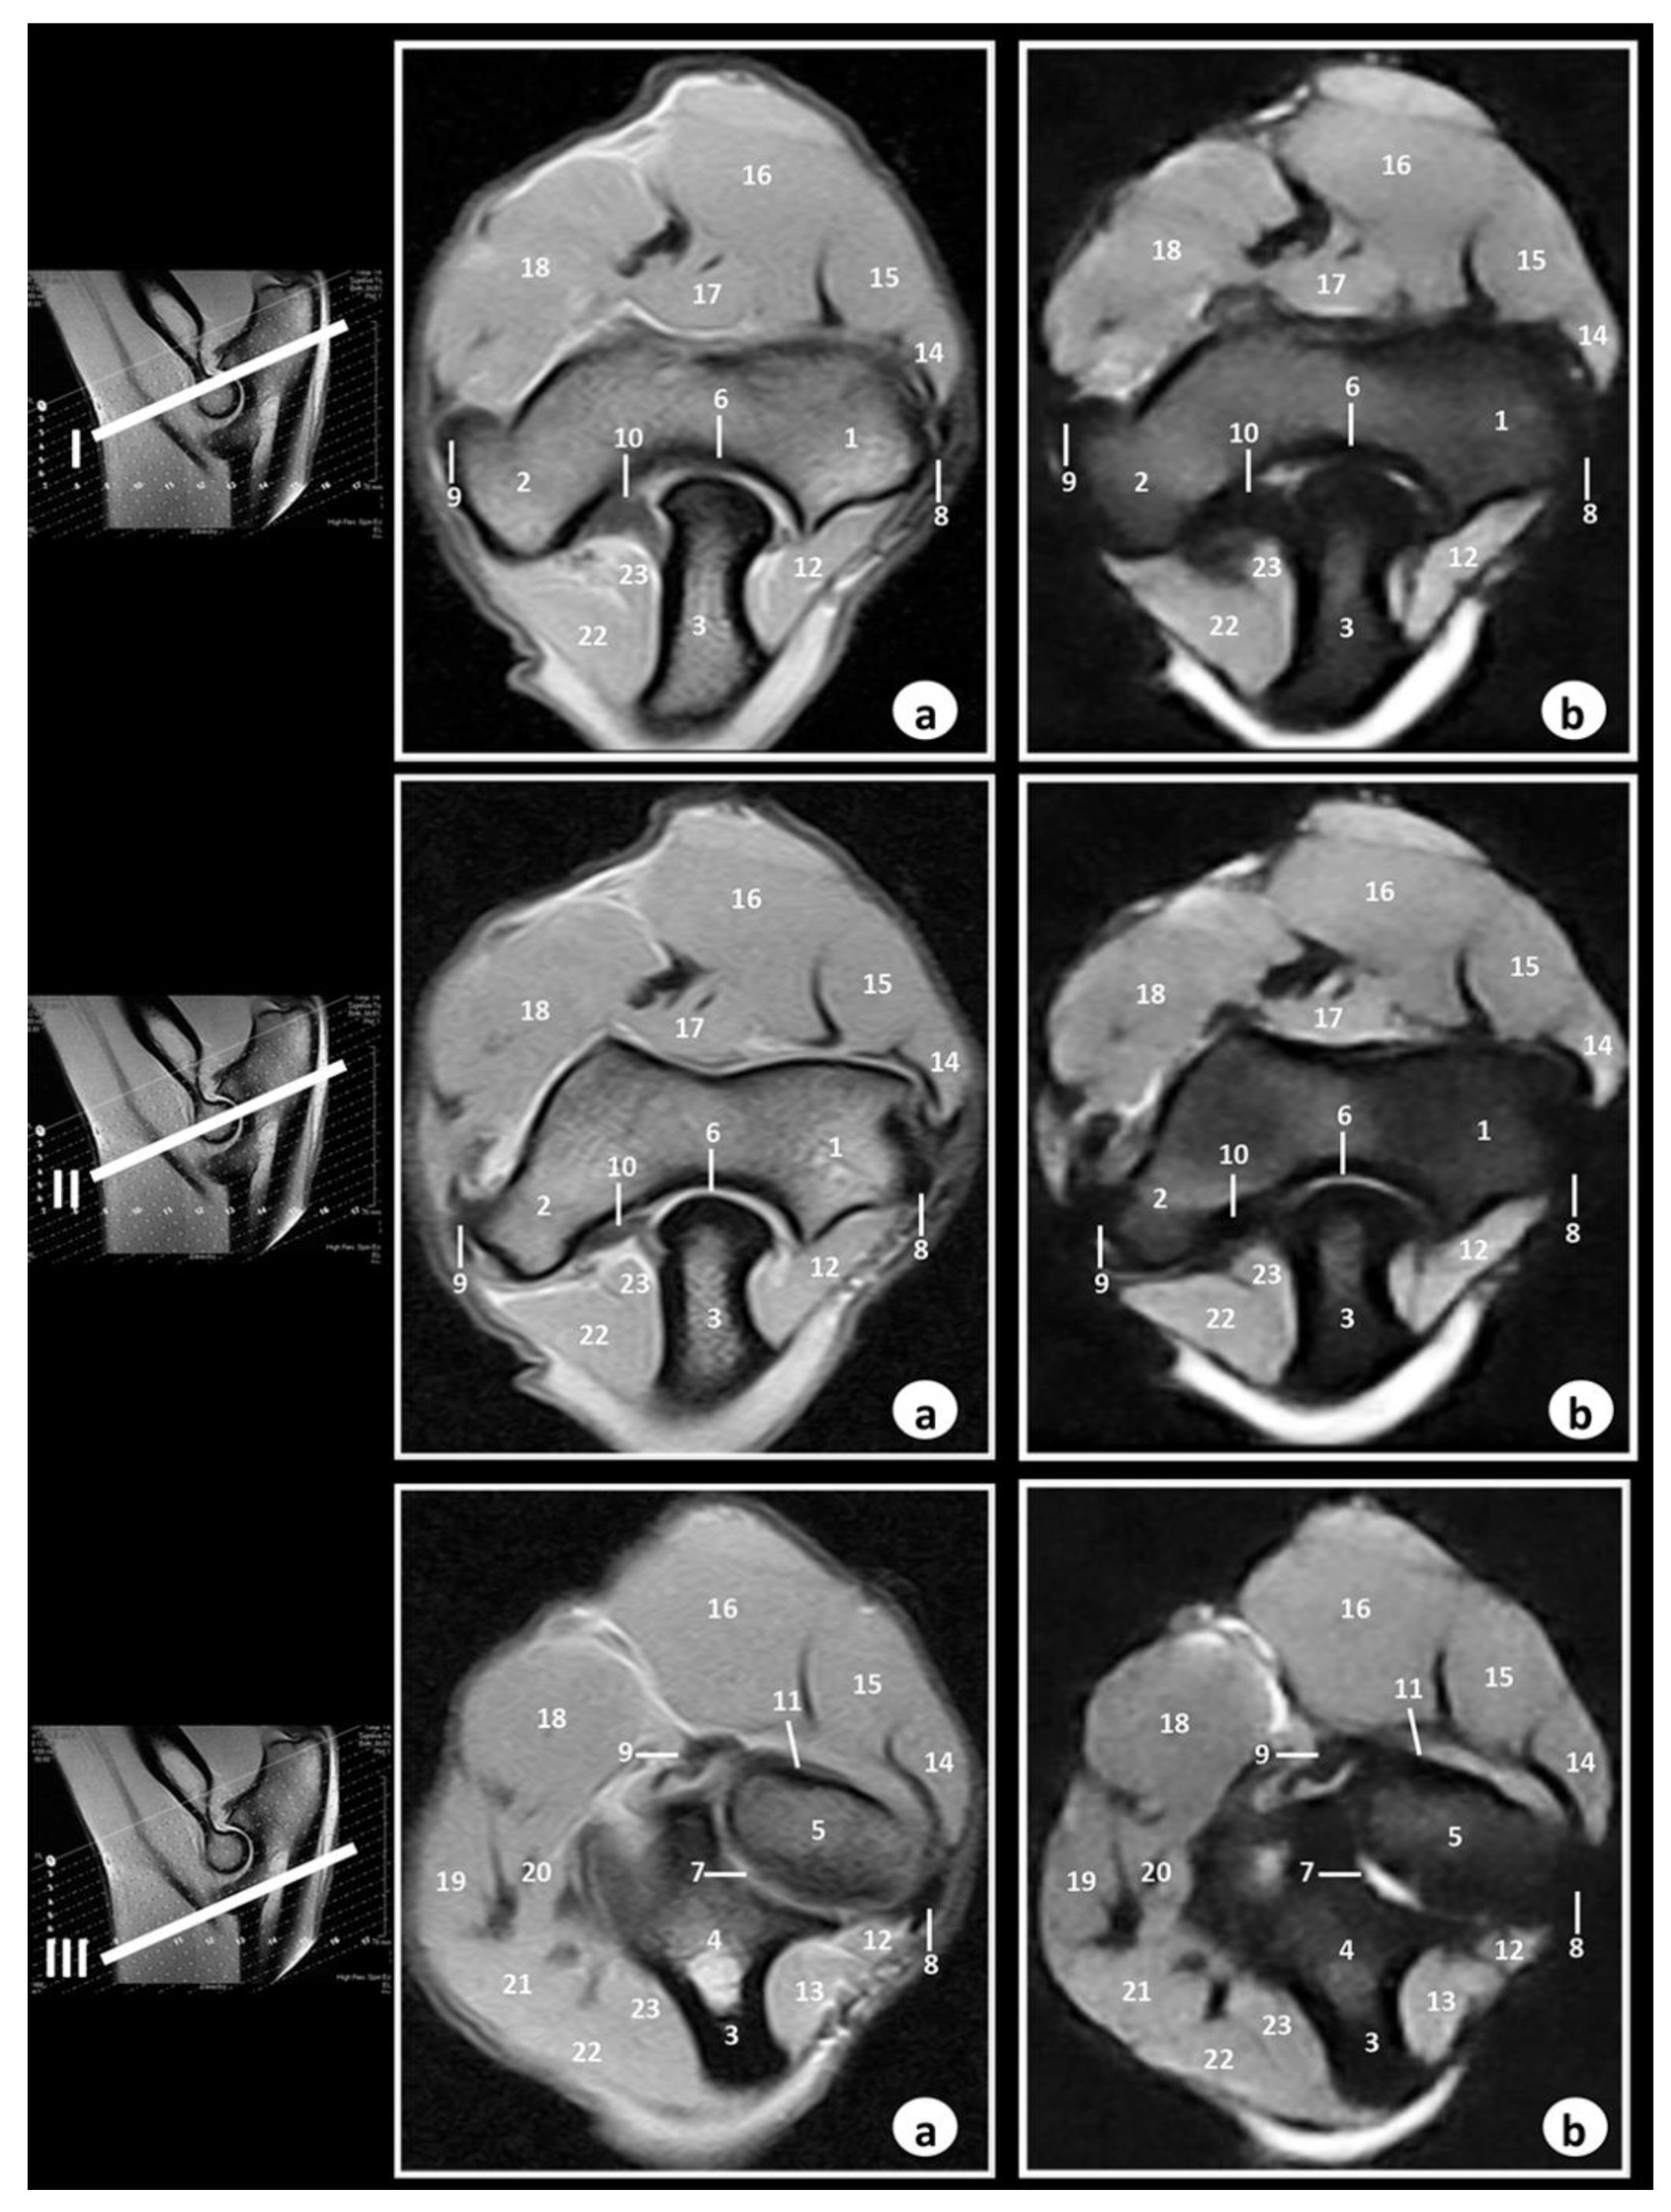

3. Results

3.2. Magnetic Resonance Imaging